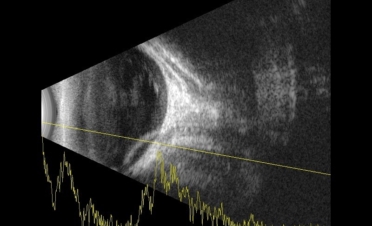

La ecografía permite observar las estructuras del globo ocular cuando la transparencia de la córnea está comprometida o cuando deseamos observar con detalle los segmentos anterior y posterior del ojo.

En ambas pruebas se observaron imágenes compatibles con un desprendimiento de retina:

Imágenes de la ecografía de Fox, un perro de raza Pomerania con desprendimiento de retina en ambos ojos. Se descartaron otro tipo de lesiones oculares. Foto: IVO. (Clicar la fotografía para ampliar)